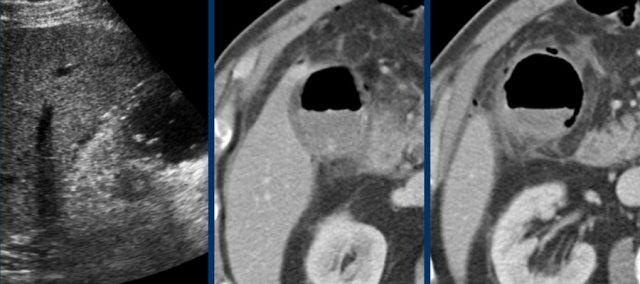

Đây là hình ảnh của một bệnh nhân béo phì với đau hạ sườn phải cấp tính trong 6 giờ. CRP 2.

Siêu âm cho thấy túi mật lớn có bùn mật, không quan sát thấy sỏi.

Việc ấn vào túi mật không đáng tin cậy do vị trí cao dưới cung sườn phải.

Không có bất thường siêu âm nào khác.

CT thực hiện cùng ngày cho thấy túi mật lớn với chỉ những thay đổi quanh túi mật kín đáo và không có nguyên nhân nào khác giải thích cho các triệu chứng.

Ngày hôm sau CRP là 105 và CT không tiêm thuốc cản quang lặp lại cho thấy quầng mờ xung quanh túi mật.

Phẫu thuật tiếp theo xác nhận viêm túi mật cấp giai đoạn sớm do sỏi nhỏ trong ống túi mật.